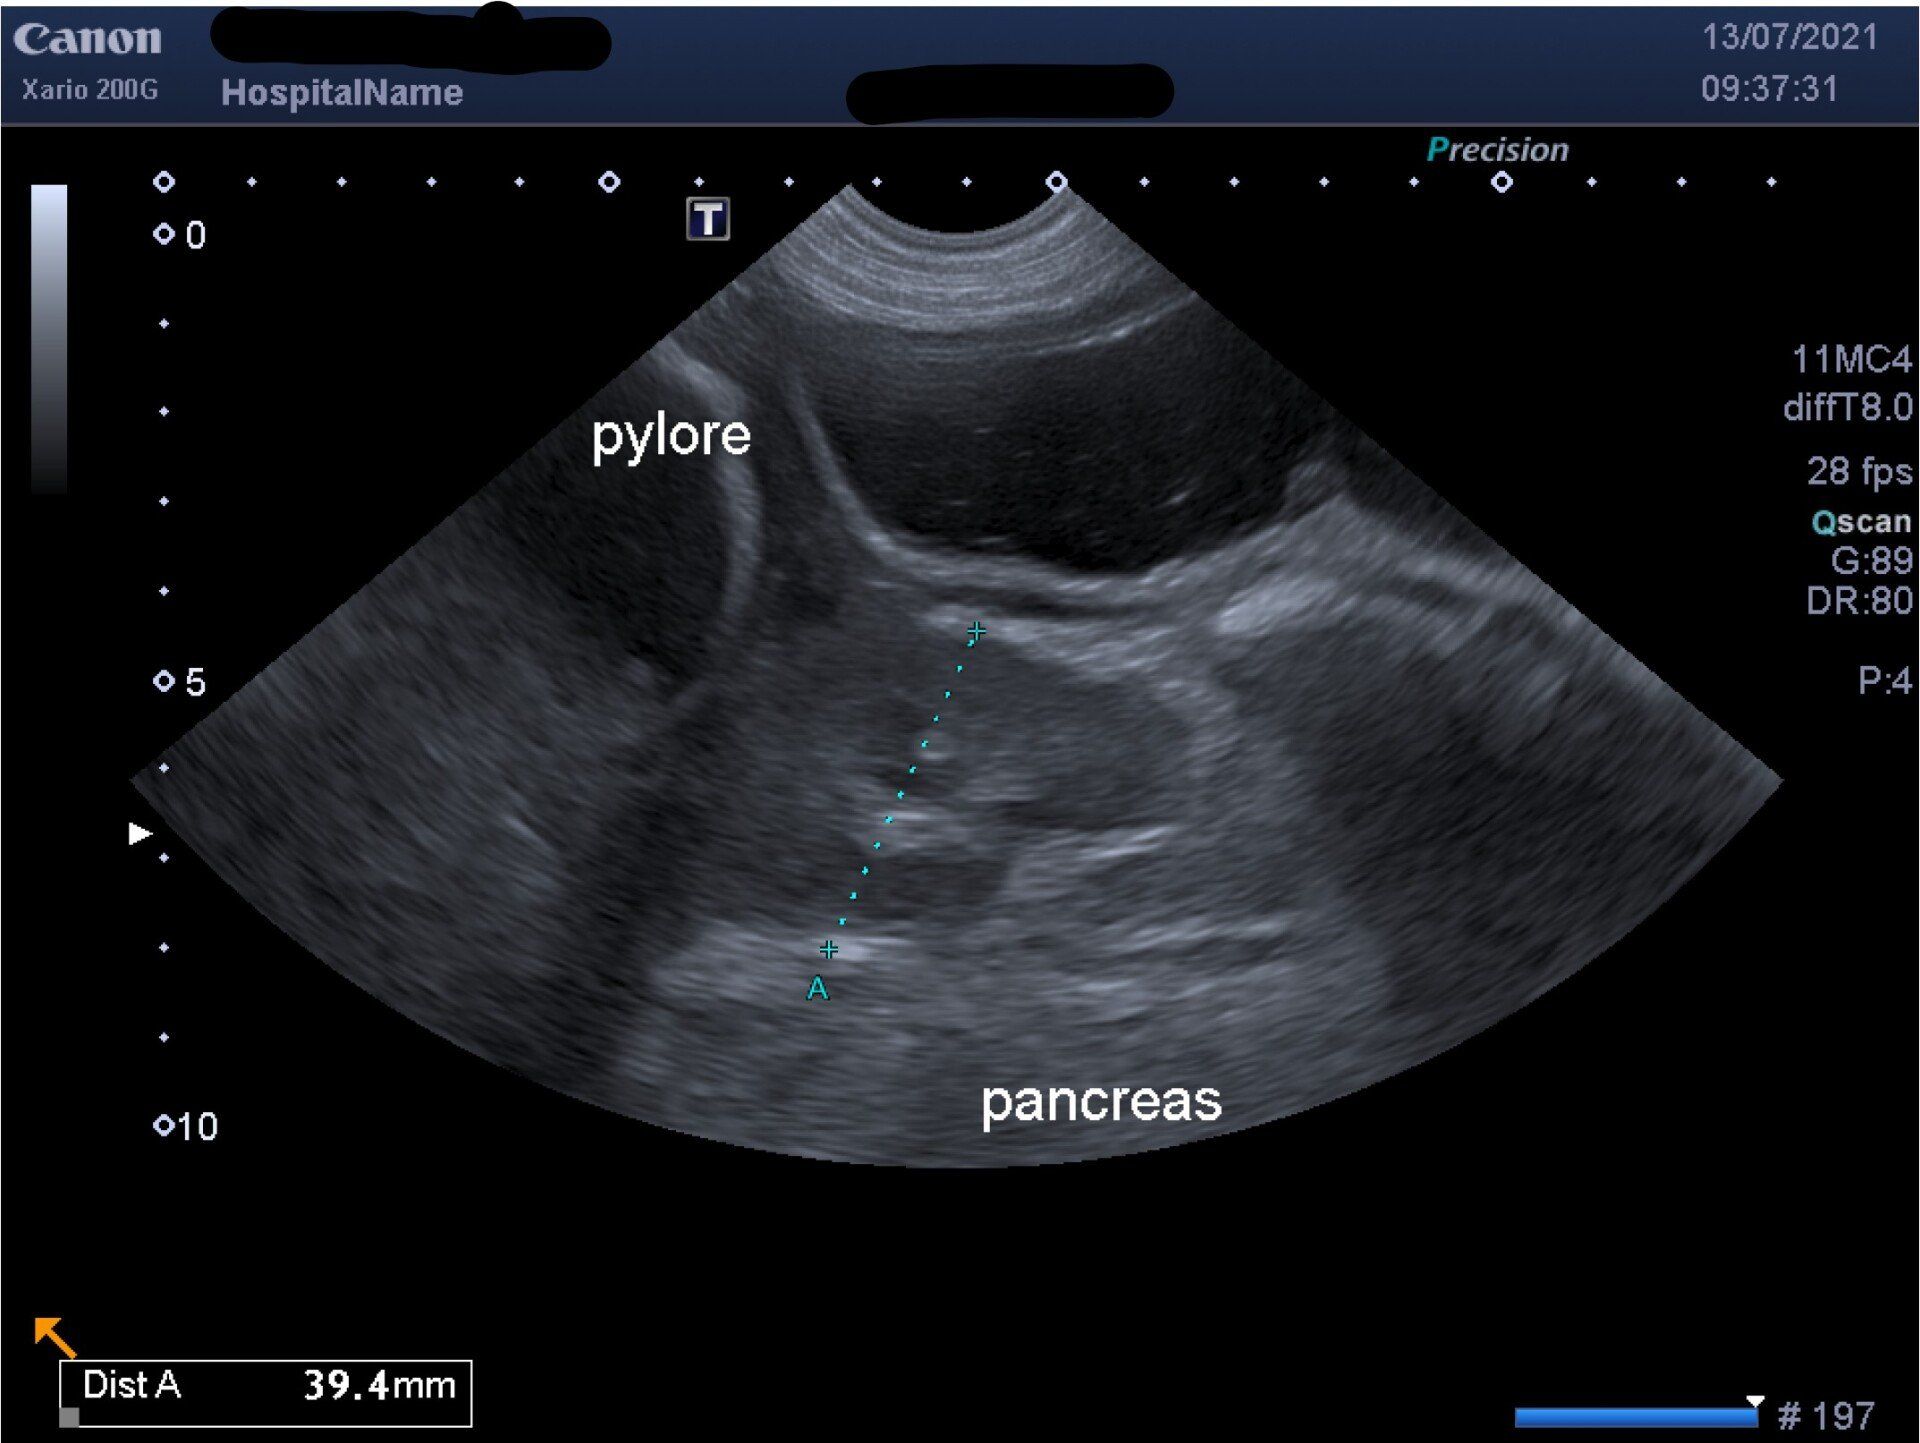

- Echographie abdominale

L'échographie abdominale est pratiquée quotidiennement au sein de nos établissements. Cette technique d'exploration permet de diagnostiquer des maladies mais également d'en suivre l'évolution à travers l'observation de la forme et de la structure des organes. Forme, dimensions, structure, aspect des différents tissus sont autant d'éléments qui vont renseigner le praticien.

Les vétérinaires vont ainsi pouvoir évaluer différents organes tels que : le foie, les reins, les glandes surrénales, les ganglions lymphatiques, l'estomac et les différents composantes du tubes digestifs, le pancréas, la rate, la vessie et le système urinaire, la prostate, le système reproducteur...

Les échographies approfondies font l'objet d'un compte-rendu synthétisant les observations du vétérinaire et des principales mesures accompagnées des images les plus pertinentes.